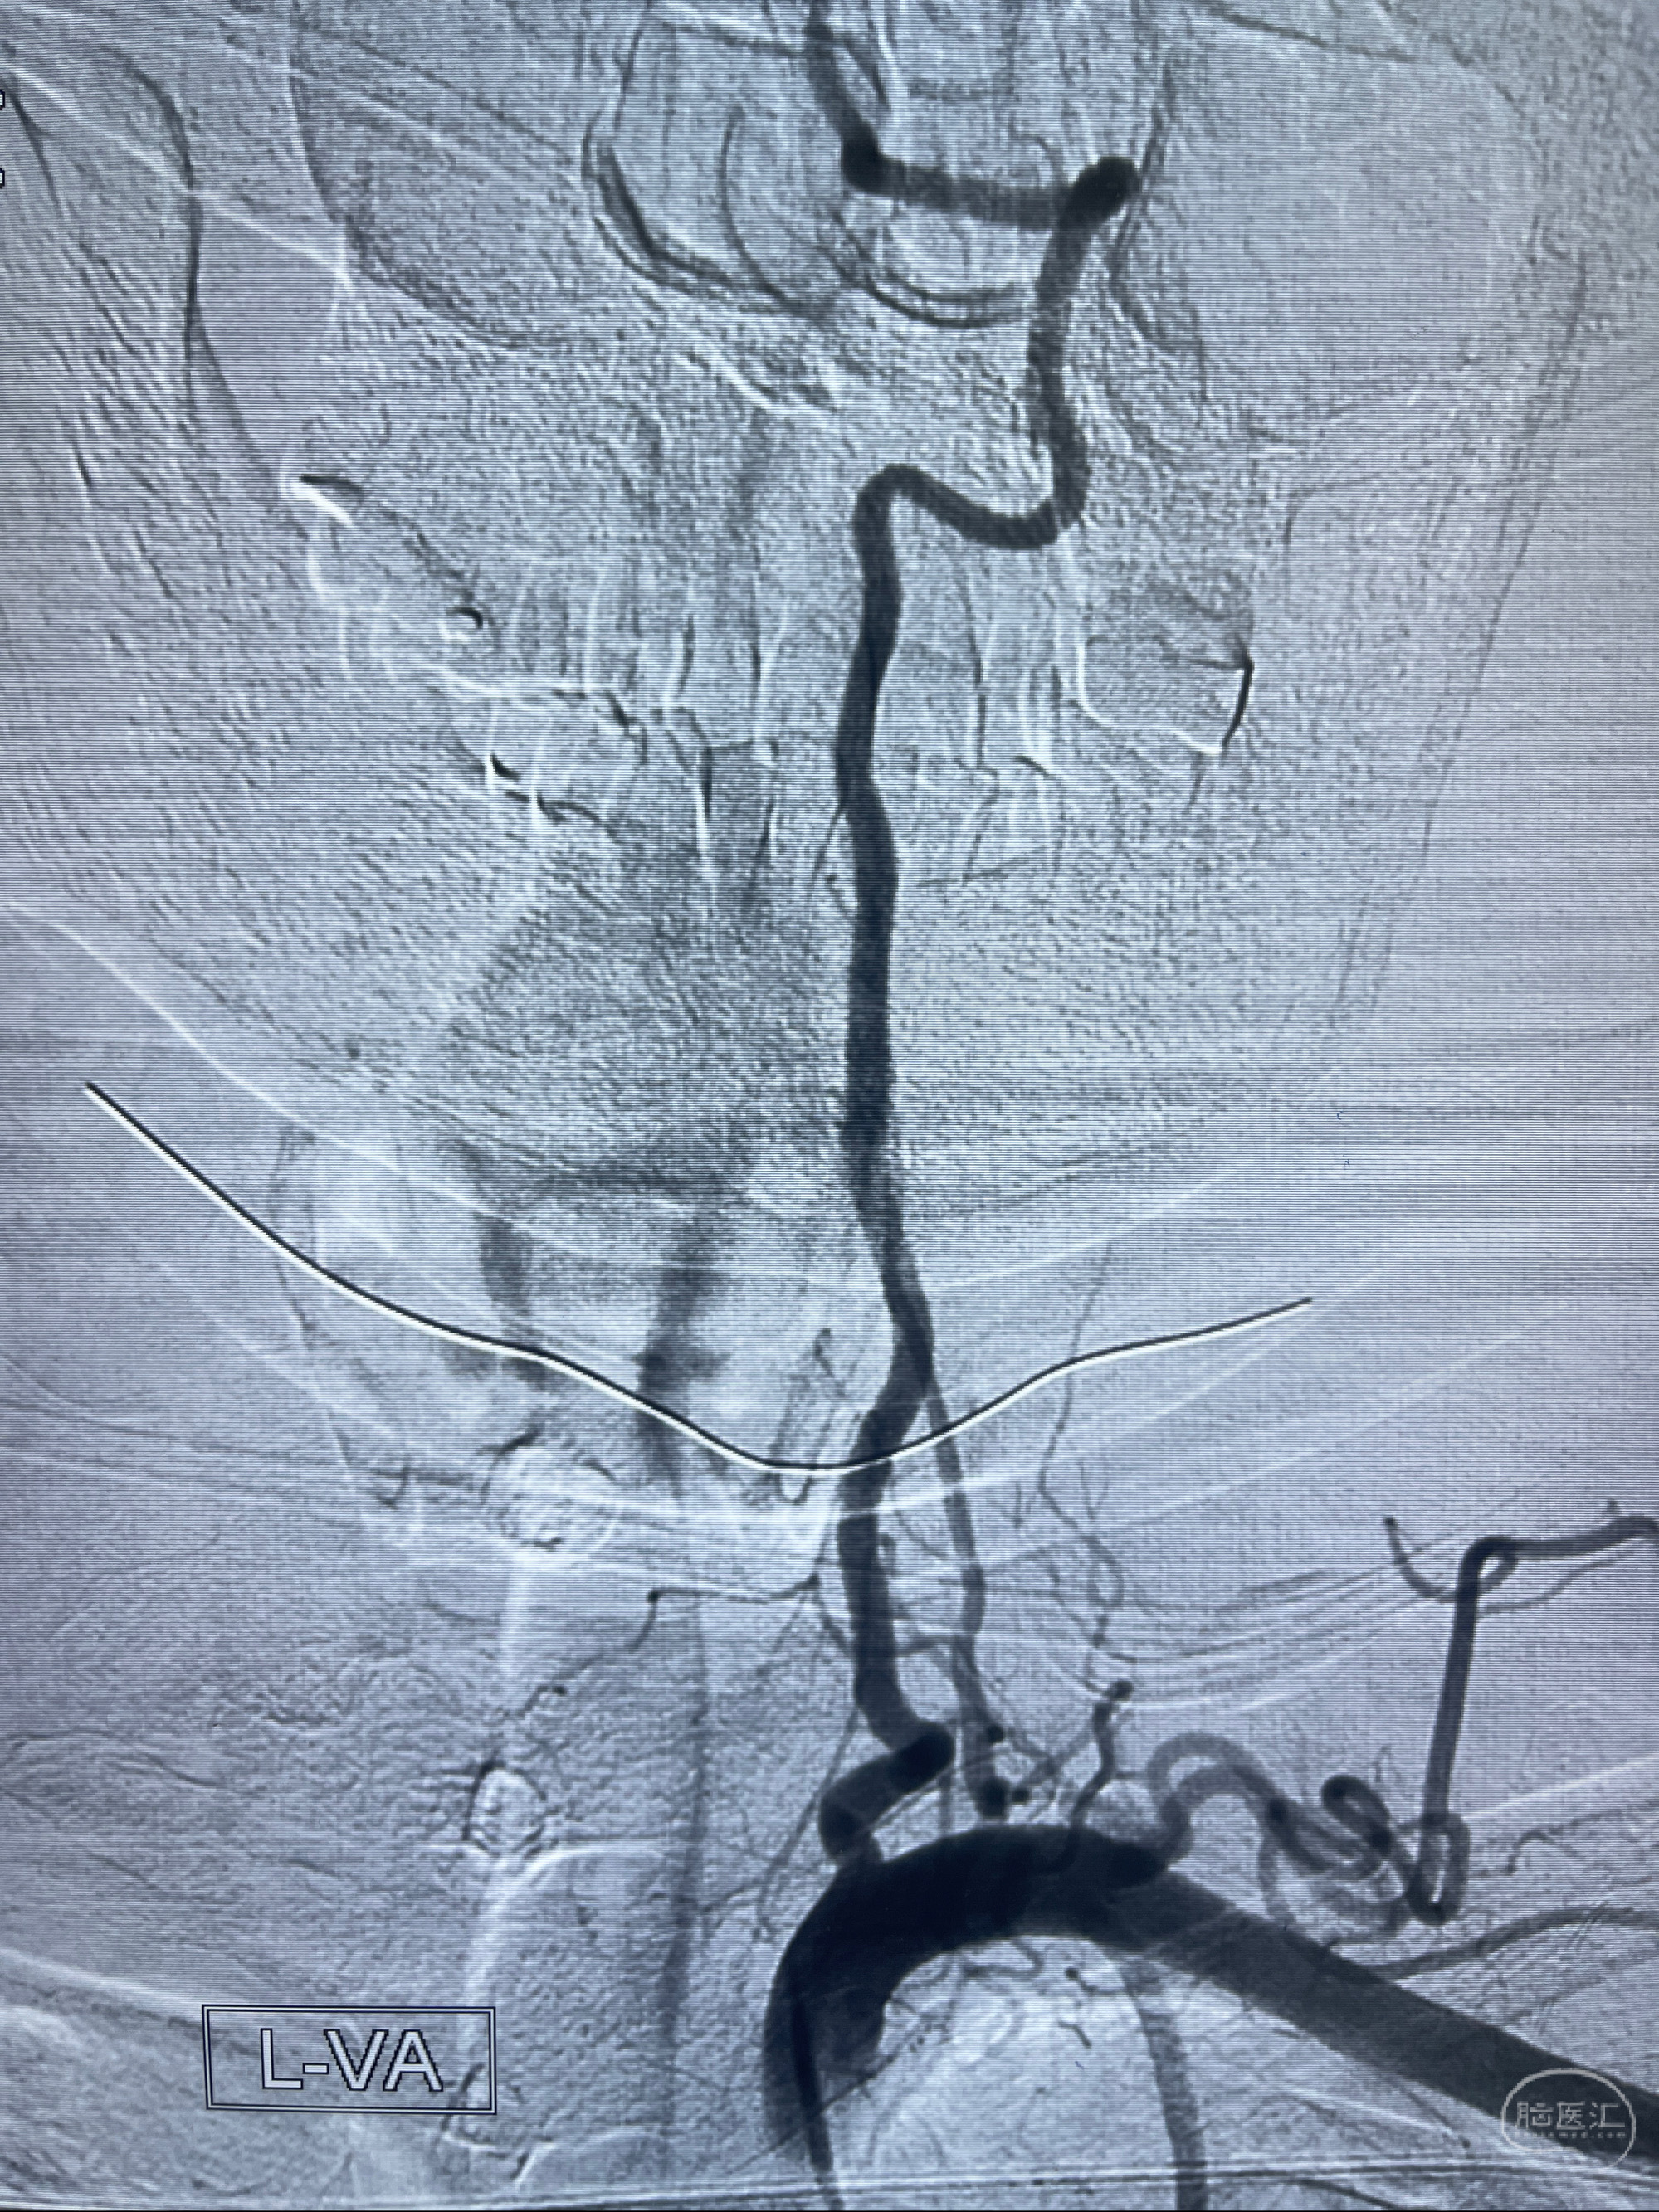

2023-02-02 沛县人民医院 头颅CTA:大脑动脉环发育变异,头颈部动脉粥样硬化,双侧颈内动脉及椎动脉颅内段多发狭窄;

1.双侧脑动脉狭窄

2.腔隙性脑梗死

2023-02-15DSA